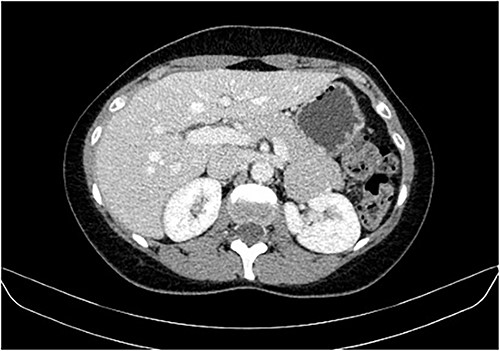

During a screening imaging examination of her liver disease, a lesion suspected of malignancy was detected. The ultrasound disclosed a hypoechoic nodule, vaguely heterogeneous, located in segment VII, subcapsular, and with ~22 mm in diameter (Fig. 1). Liver blood tests and serum alpha-fetoprotein level were normal. For better characterization, a CT scan was performed. The CT showed, in addition to signs of chronic liver disease, the presence of a solid subcapsular nodule of segment VII, measuring 23 mm, with hypervascular behavior in the arterial phase (Fig. 2) and washout in late venous phase (Fig. 3).

CT scan showing the same mass as shown in Fig. 2 but with washout in the portal venous phase.